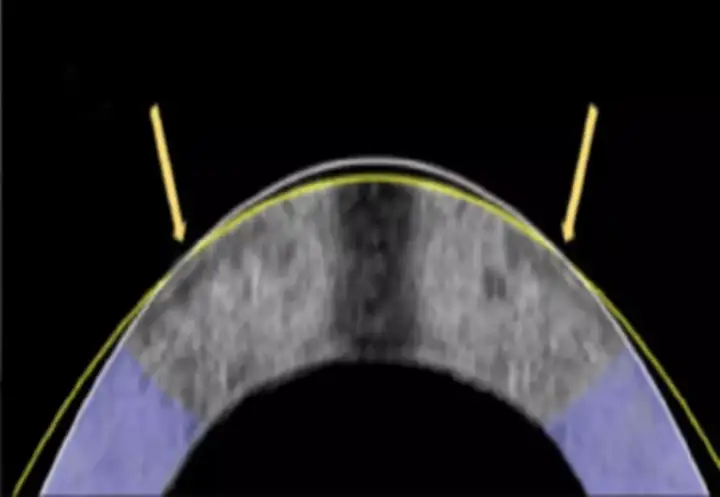

Новый метод, позволяющий ремоделировать роговицу посредством слабого электрического потенциала, известен как электромеханическое изменение формы. Роговица — это прозрачная куполообразная поверхность в передней части глаза, действующая как прозрачное окно, помогающее фокусировать входящий свет. Она состоит из плотно упакованных коллагеновых волокон и отличается прочностью и гладкостью. Это естественная линза глаза, и именно здесь происходит преломление света, необходимое для фокусировки изображения на сетчатке.

Кривизна роговицы приводит к таким состояниям, как близорукость (миопия) и дальнозоркость (гиперметропия), и до сих пор основным методом лечения этих заболеваний был лазерный кератомилёз. Это дорогостоящая и инвазивная процедура, поэтому вместо этого исследователи предложили работать с самим составом роговицы, чтобы изменить форму купола. Учёные обнаружили, что, пропуская слабый электрический ток через специально разработанный платиновый электрод, можно изменить pH ткани, повышая её кислотность и делая её гибкой ровно настолько, чтобы её можно было изменить.

Затем, как только ток прекращается, а pH возвращается к норме, роговица снова затвердевает и сохраняет заданную форму. Весь процесс занимает около минуты, не требует разрезания или удаления ткани, и на данный момент не выявил структурных повреждений или гибели клеток в исследованных образцах. Авторы методики уже протестировали процесс на 12 кроликах, изменив форму глаз у 10 из них, и в итоге каждая роговица приняла необходимую форму. Хотя лечение при помощи электричества пока находится на ранней стадии разработки, оно вполне может в будущем заменить лазерную коррекцию.